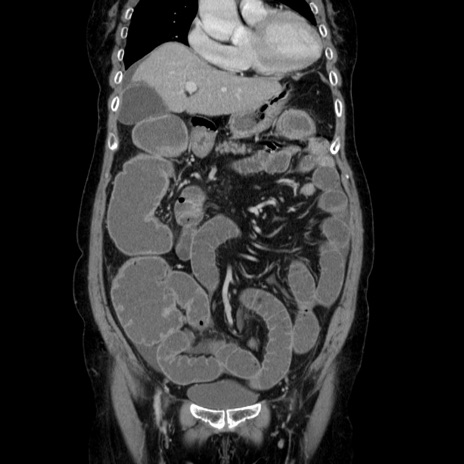

症例5(冠状断像)

【症例】70歳代女性

【主訴】お腹が張る

【現病歴】1週間くらい前から腹部膨満の自覚あり。昨日夜から増悪したため、本日救急外来受診。

【身体所見】意識清明、BT 36.5℃、BP 165/106mmHg、HR 80bpm、SpO2 98%、腹部:膨満、軟、自発痛・圧痛なし、触診にて不快感あり、腸蠕動音:減弱

【データ】WBC 12600、CRP 1.04